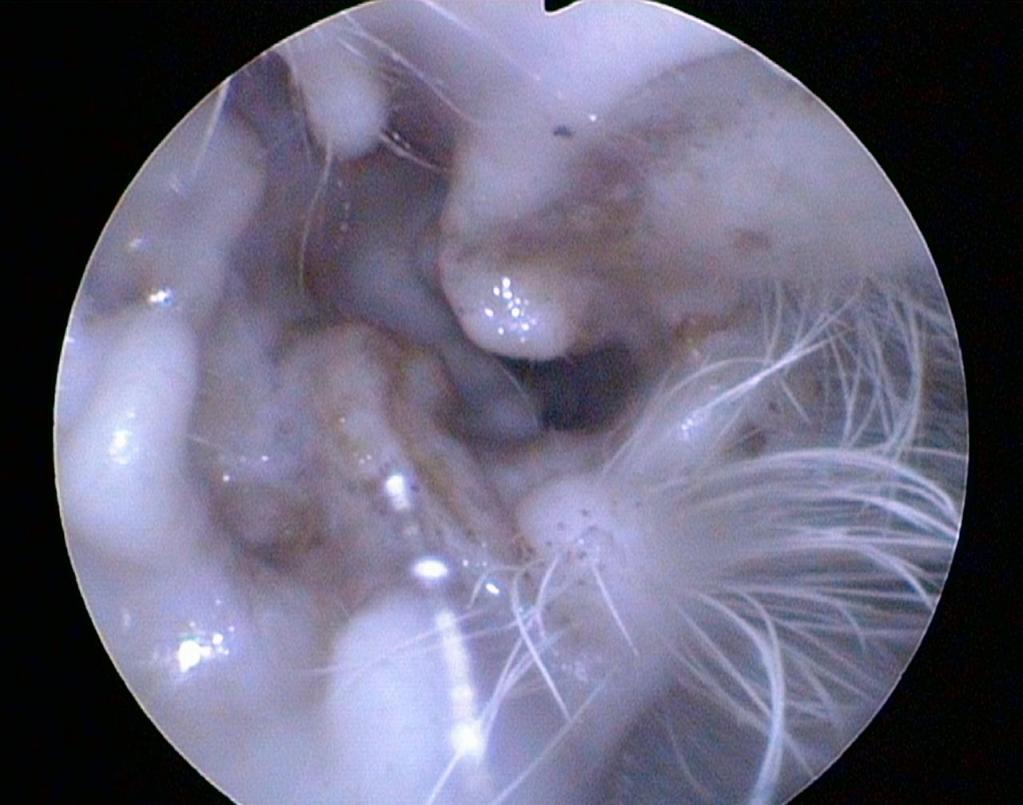

Ist eine darüber hinaus reichende Untersuchung des äußeren Gehörganges notwendig, umfasst diese die Probenentnahme zur weiteren Diagnostik. Dies ist in vielen Fällen für den Patienten schonend endoskopisch möglich.